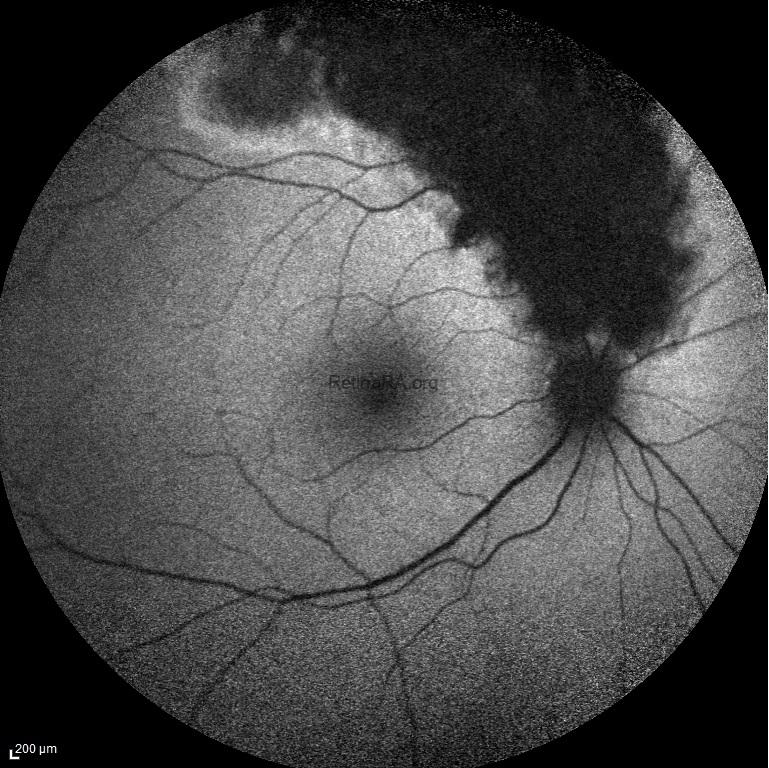

Traumatic pigmentary retinopathy was detected in a 38-year-old male with a history of blunt eye trauma and hyphema. The ophthalmic evaluation of the left eye was normal. His visual acuity was 20/20 bilaterally. Color fundus photograph, fundus autofluorescence image, infrared reflectance image, and blue reflectance image of the right eye show pigmentary changes at the anterior of the superior-temporal arcade simulating “sector retinitis pigmentosa”.

Blue reflectance image of traumatic pigmentary retinopathy